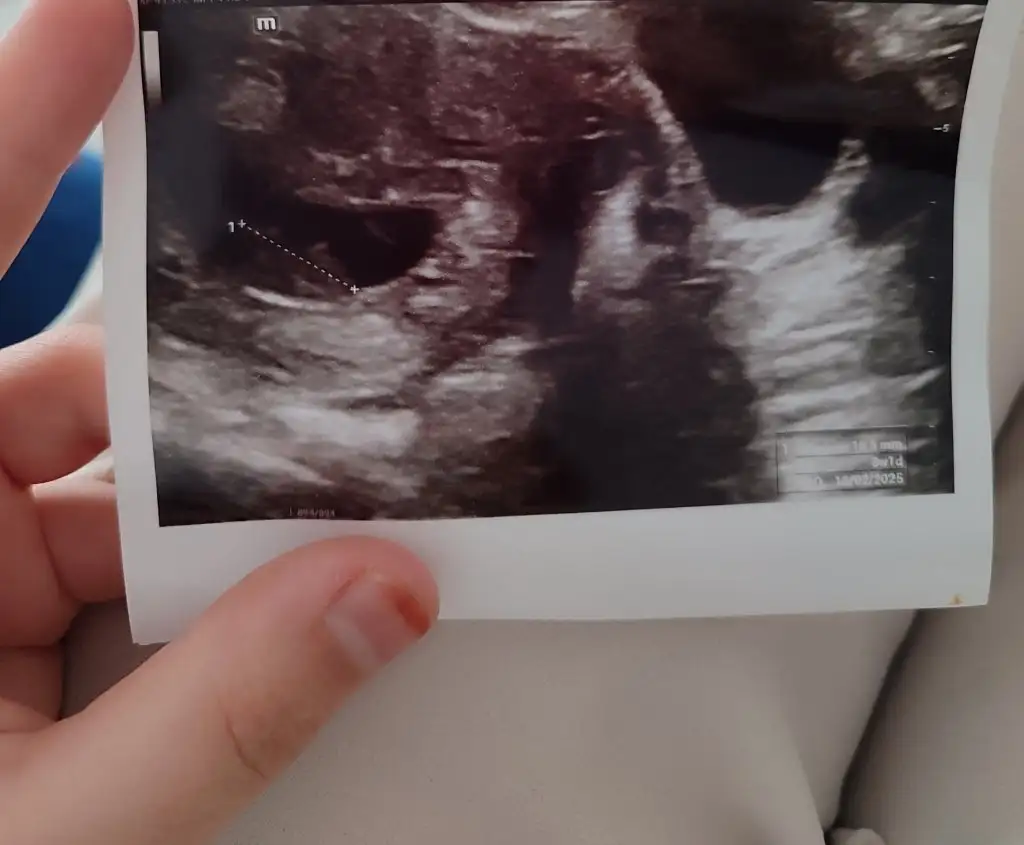

Çok merak ediyorum cinsiyet tahmini yapar mısınız rica etsem

13 haftalık cinsiyet tahmini yapabilir misiniz